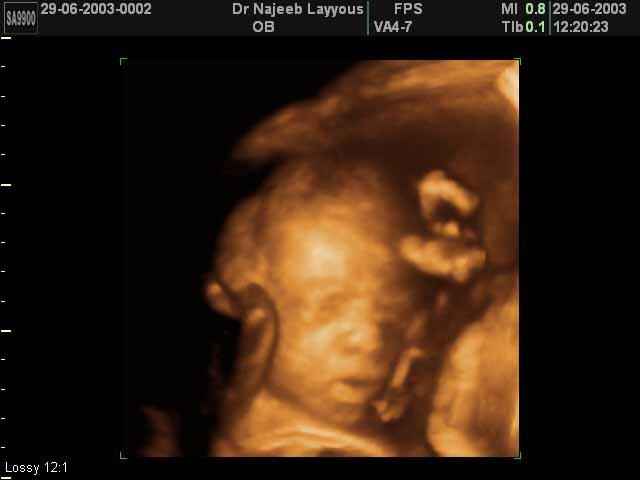

- 3D Fetal Profile Ultrasound Scan Photos

3D Fetal Face Ultrasound Scan Photos | Dr N Layyous